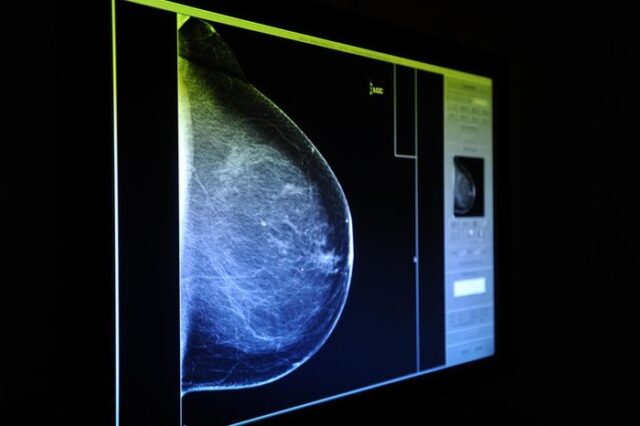

Projeto aprovado na Câmara de Porto Alegre permite realização de mamografia pelo SUS por mulheres com menos de 50 anos

PL que garante acesso aos exames foi aprovado na Câmara de Vereadores e aguarda sanção do prefeito Um projeto de lei aprovado na Câmara de Vereadores de Porto Alegre prevê que todas as mulheres residentes em Porto Alegre possam realizar procedimentos como mamografia bilateral de rastreamento e ultrassonografia mamária por meio do Sistema Único de Saúde…